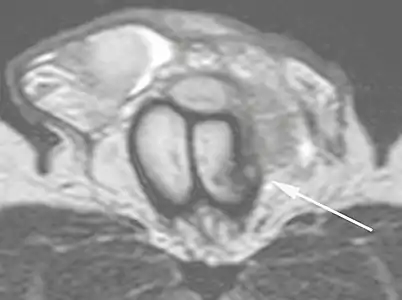

Ultrasound examination is able to depict the tunica albuginea tear in the majority of cases (as a hypoechoic discontinuity in the normally echogenic tunica). In a study on 25 patients, Zare Mehrjardi et al. concluded that ultrasound is unable to find the tear just when it is located at the penile base. In their study magnetic resonance imaging (MRI) accurately diagnosed all of the tears (as a discontinuity in the normally low signal tunica on both T1- and T2-weighted sequences). They concluded that ultrasound should be considered as the initial imaging method, and MRI can be helpful in cases that ultrasound does not depict any tear but clinical suspicions for fracture are still high. In the same study, authors investigated accuracy of ultrasound and MRI for determining the tear location (mapping of fracture) in order to perform a tailored surgical repair. MRI was more accurate than ultrasound for this purpose, but ultrasound mapping was well correlated with surgical results in cases where the tear was clearly visualized on ultrasound exam.[10] The advantage of ultrasound in the diagnosis of penile fracture is unrivaled when its noninvasive, cost-effective, and nonionising nature are considered.[11]

In the ultrasound examination, a lesion of the tunica albuginea presents as an interruption in (loss of continuity of) the echoic line representing it (Figure 4). Small, moderate, or broad hematomas demonstrate the extent of that discontinuity. Intracavernous hematomas, sometimes without the presence of a tunica albuginea fracture, can be observed when there is a lesion of the smooth muscle of the trabeculae surrounding the sinusoid spaces or the subtunical venular plexus.[2]

B: Axial T2-weighted turbo spin-echo magnetic resonance imaging scan showing left-sided discontinuity of the tunica albuginea (arrow), secondary to fracture.[2]